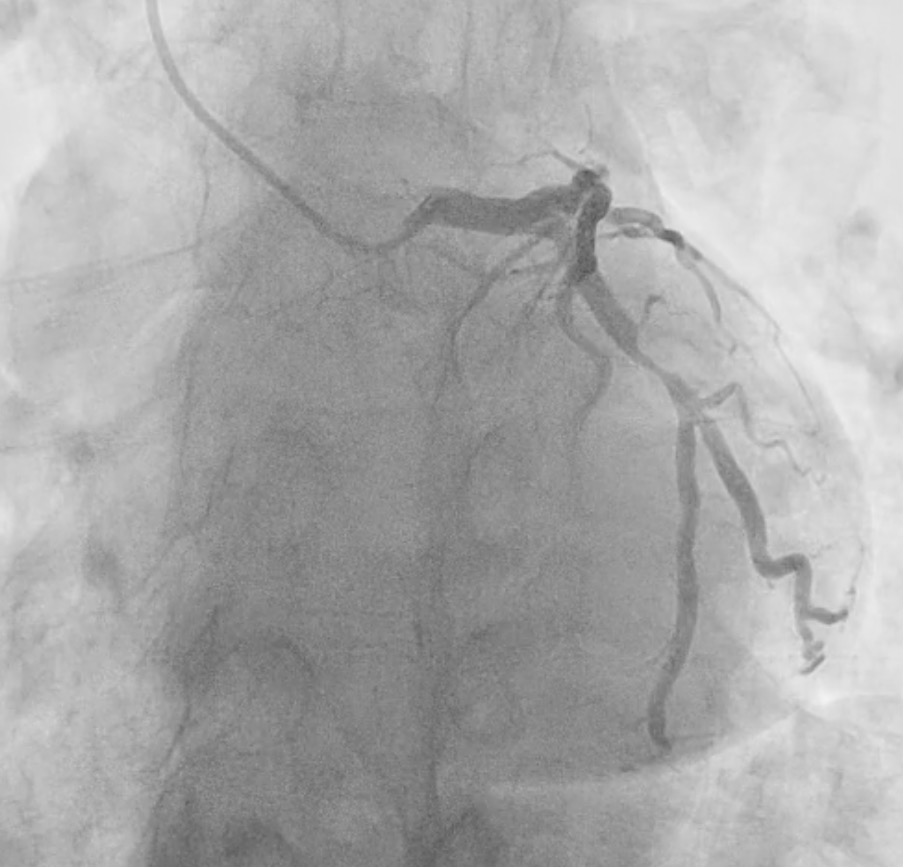

Coronary angiogram showed 90% stenosis of mid-LCX (Video 1). The maximum radial wall strain (RWS) was 26%, reflecting significant plaque vulnerability (>12%). Murray law-based quantitative flow ratio analysis (¥ìFR) was 0.50 (Figure 1), reflecting functional significance (<0.80). Optical coherence tomography (OCT) showed fibroatheroma with lipid arc of 270 degrees with mild calcification (Video 2). Overall, the findings were consistent with vulnerable plaque at mLCx.